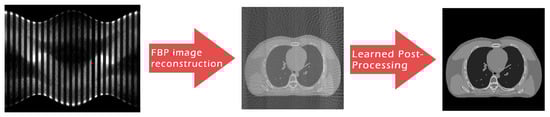

However, even in this case, the visual inspection is not fully consistent with the metrics since the reconstruction obtained by 3L-SSNet with half-range geometry shows the highest quality. In Figure 8 (half-range geometry), the image in Figure 8b learned by 3L-SSNet is less noisy than the crop in Figure 8a from ResUNet; in the second zoom, the low contrast objects pointed by the arrow are far more contrasted in the 3L-SSNet reconstruction in Figure 8c than in the ResUNet (Figure 8d). Moreover, a noisy pattern is still visible inside the dark background of the lungs in Figure 8c, reflecting the difficulty of the residual network in handling unseen noise.

Figure 8. Crops of the reconstructions of the test patient with unseen noise and half-range geometry. ResUNet in (a,c), 3L-SSNet in (b,d).